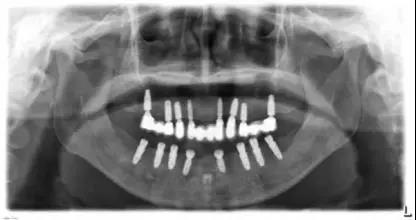

完善的术前准备对于咬合重建的成功至关重要,包括咬合分析和修复计划。通过临床和影像学检查,了解患者现有口腔条件对种植修复预后的影响。需特别注意易造成修复失败的因素,如系统性疾病、牙周病等,应先完成相应的治疗。咬合分析是根据患者的咬合垂直距离和颌位,以及咀嚼肌和颞下颌关节等情况,确定是否适合咬合重建,确定是单颌还是双颌进行咬合重建。然后对患者的咬合功能和美学进行评估,并为患者拟定可供选择的修复治疗计划。

咬合重建修复由于涉及整个牙列牙体形态、咬合关系、颌位、咀嚼肌、颞下颌关节位置等的改变,通常需要多个临床学科的通力合作。其中,准确的确定并记录无牙颌患者的颌位关系,是种植全口义齿修复的关键。目前,有学者认为无牙颌咬合重建应在正中关系位(centricrelation,CR)建牙合,因此位置稳定、重复性高,独立于天然牙列而存在,且颞下颌关节韧带处于舒适的状态,故可作为种植全口义齿修复时的参考记录位。

X线片头影测量法是将牙、颌、颅面上各标志点描绘出一定的线和角并进行分析,从而反映牙、颌、颅面软硬组织结构情况。通过该技术可建立不同人群的测量数据库,量化分析各项指标,寻找与咬合垂直距离相关的骨性结构并建立回归方程,从而计算出患者原有的咬合垂直距离或咬合重建中需升高的垂直距离。